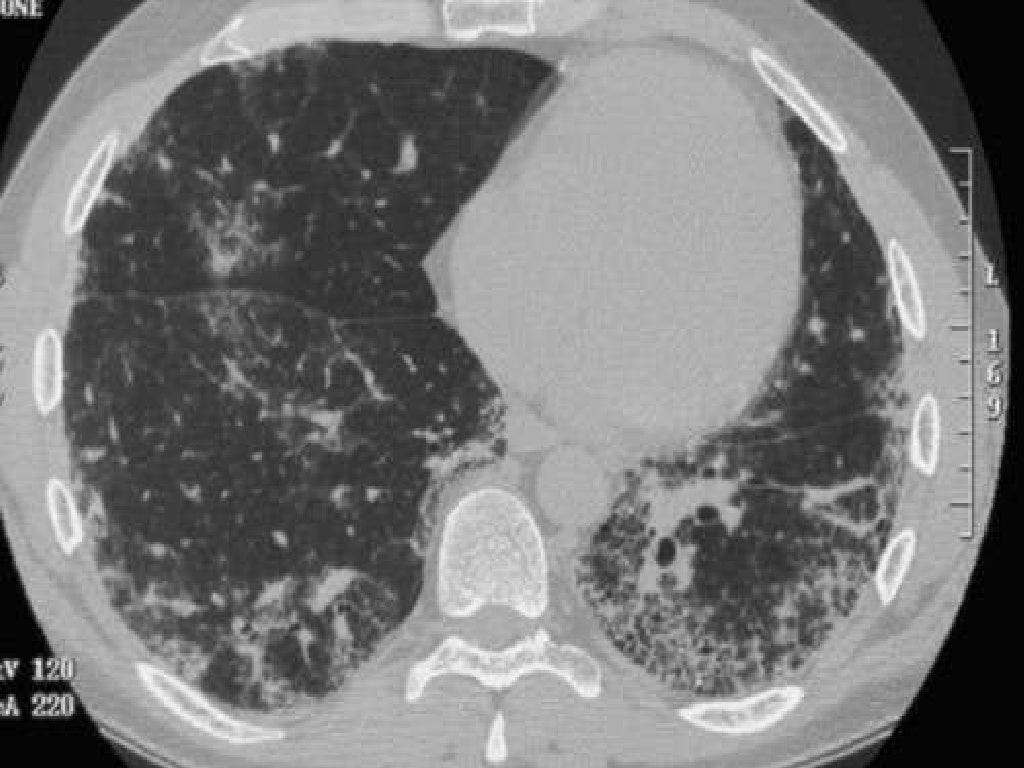

From www.ctchestreview.com

Case 47 When Does RB RBILD and RBILDFibrosis? Smoking Related Ild Radiology >95% of patients are actively smoking. There is strong evidence supporting a causal role for cigarette smoking in development of respiratory bronchiolitis ild (rb. At histological level, smoking causes a process of inflammation, destruction and subsequent lung remodelling, and is a risk. In this article, we describe and illustrate the characteristic clinical features, imaging findings, and pathologic findings of diffuse. Smoking Related Ild Radiology.